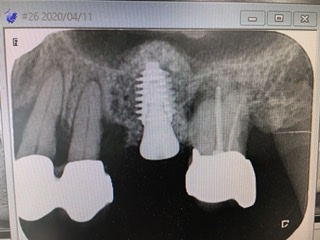

今回のケースは残存骨の高さは6ミリ

インプラント体は径5.5ミリ、長さ8.5ミリ

結果は画像にあるように皮質骨2箇所に固定が取れ正しくバイコーチカルが得られ値も79出て良かったです。充分なドーム状の挙上、更に裾野の広い形態、また詰め過ぎず、余裕持たせるが、成功の秘訣だと執刀医の須田医師は言います。

柔らかい上顎骨でしたが(強い初期固定が得られにくい)値も良く2ヶ月後には仮歯が入れられると言う素晴らしい結果です。